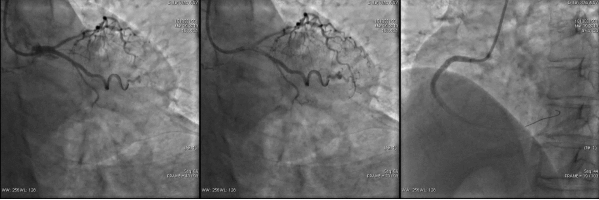

第二次手术过程

手术时间: 2014年8月。

造影结果: LAD病变较前未见明显变化,RCA次全闭塞,LCX支架内100%闭塞。

![]()

手术过程: 再次支架植入,效果良好恢复血流,TIMI3级。